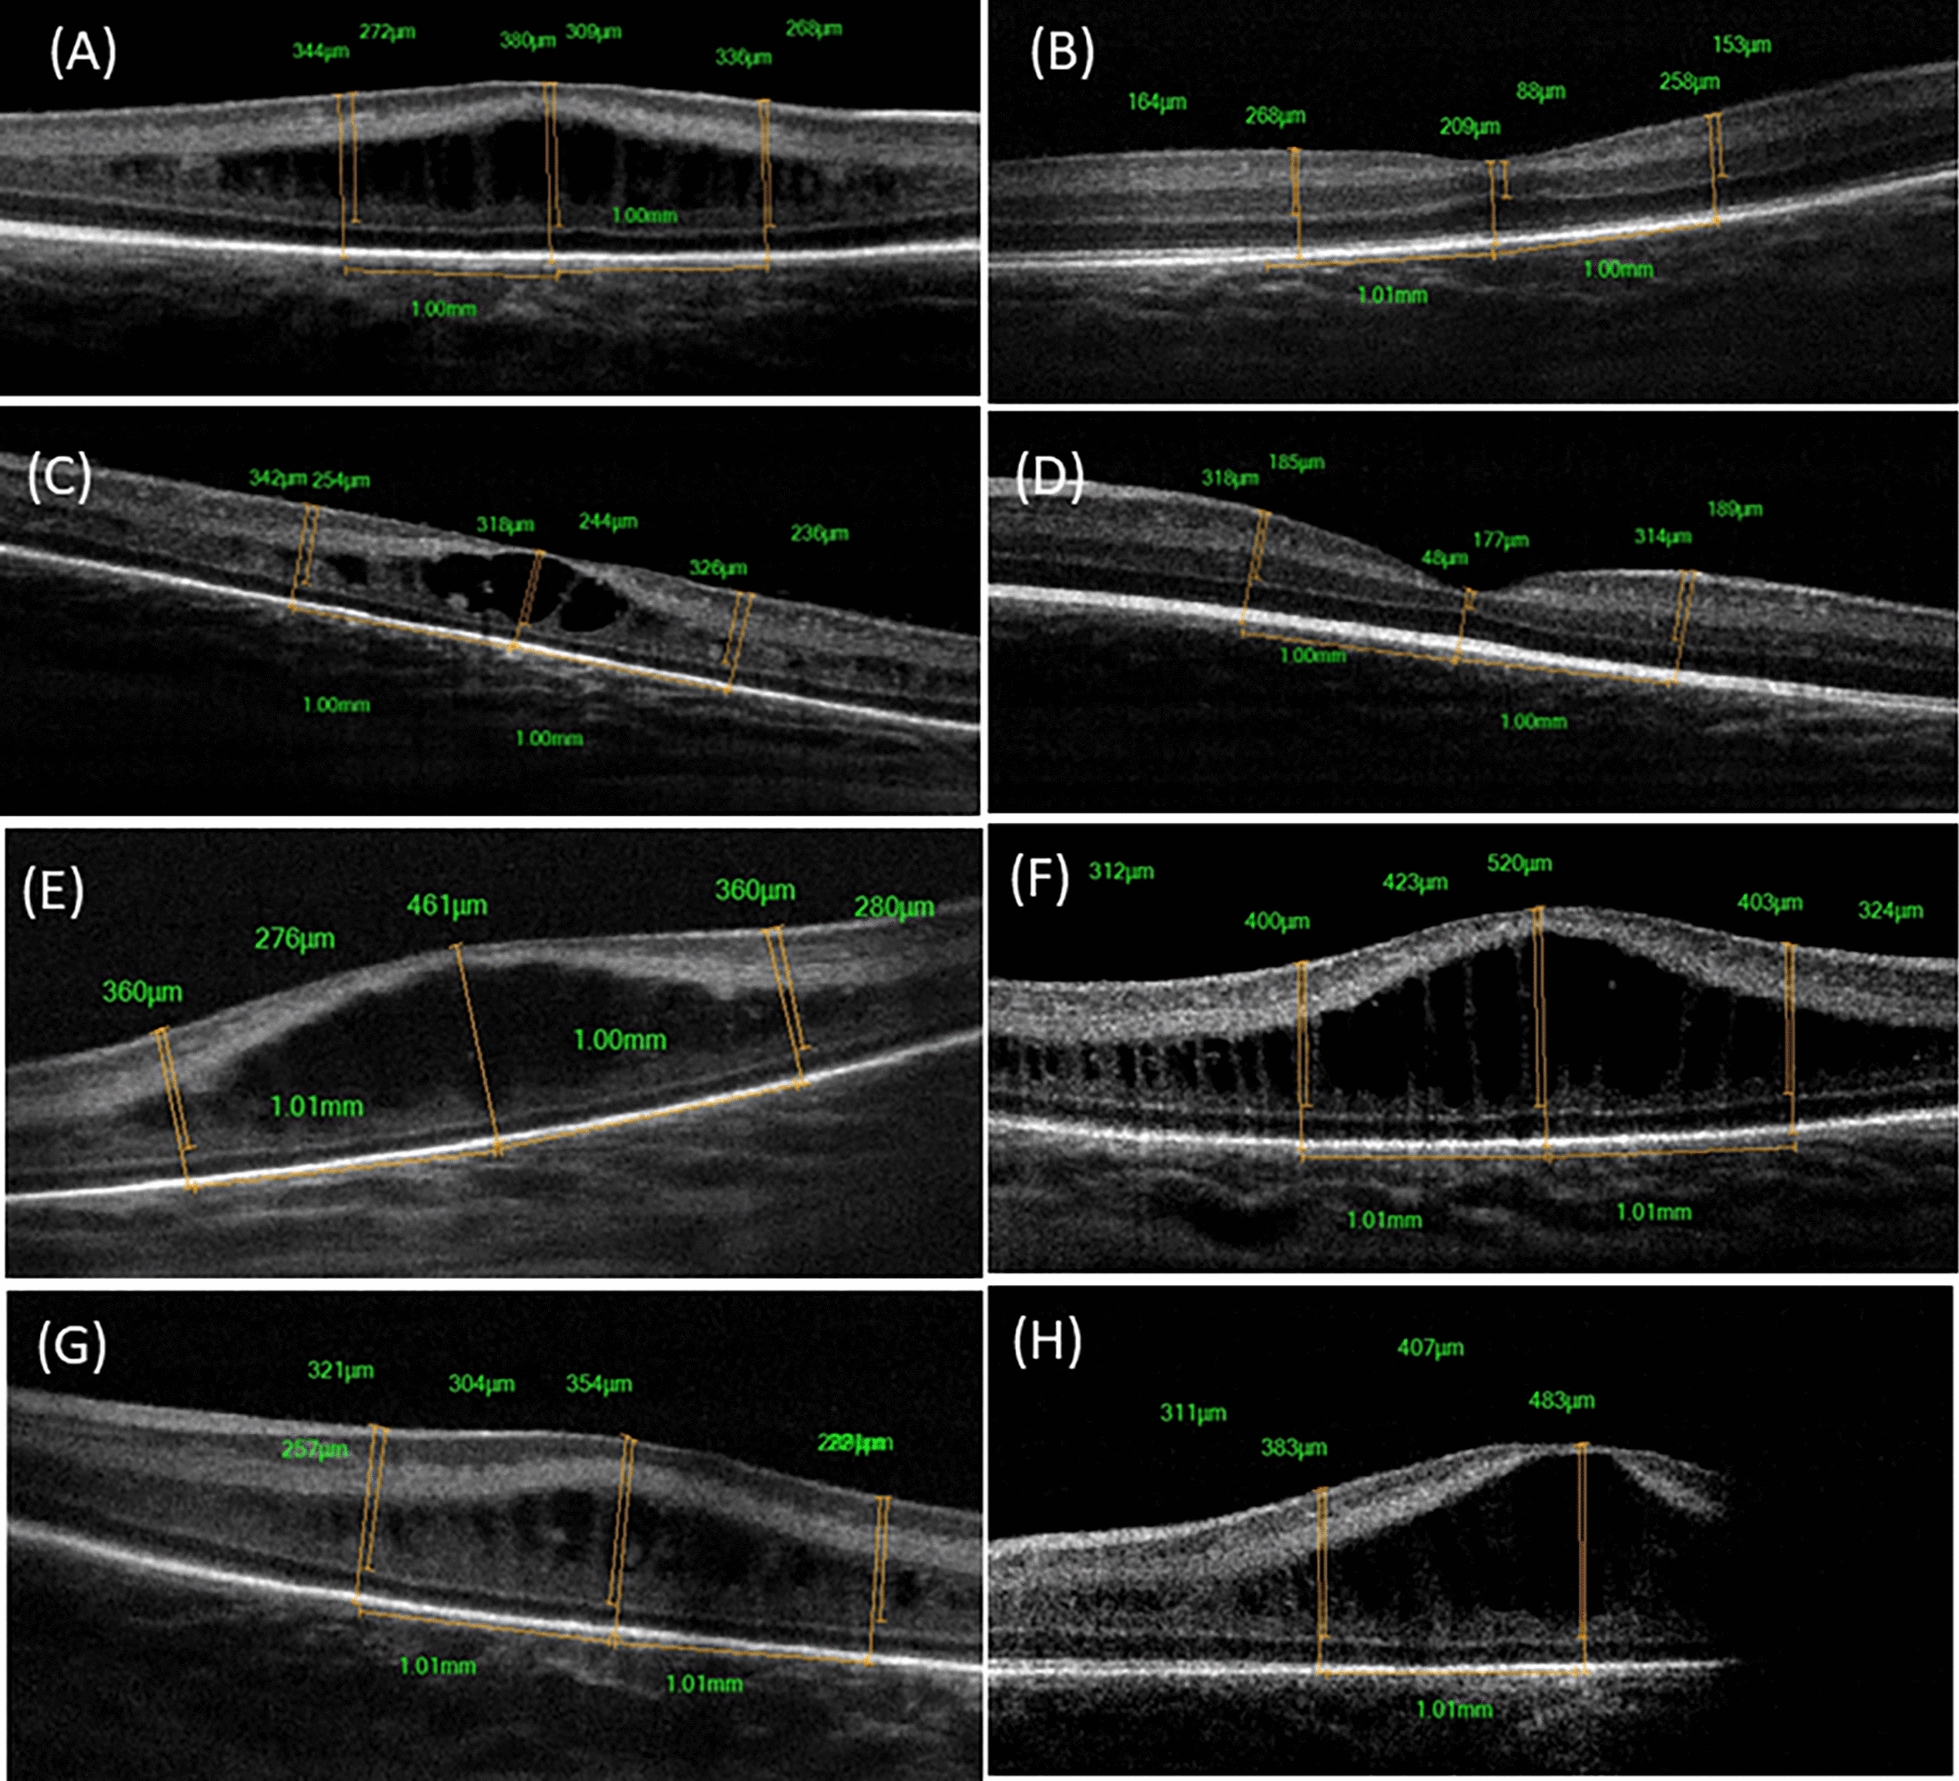

Methods: Preterm infants with type 1 ROP indicated for Ranibizumab injections were included in this study. Handheld OCT imaging was performed at baseline, 1 week, and 1 month post injection. Central full thickness (CFT), inner retinal layer (IRL), and outer retinal layer (ORL) thickness measurements were taken from foveal center and parafoveal region.

Results: 24 eyes of 12 infants were included in this study. There were no significant changes in the mean CFT and IRL thickness at 1 month (p = 0.5 and 0.1 respectively). However, there was significant increase in the mean ORL thickness at 1 month (69.9 ± 16, 96.1 ± 25 at baseline and one month respectively, p < 0.001), with differentiation (appearance of IS/OS junction ± ELM) in 55.6% of eyes. Macular edema (ME) was observed in 12 eyes (50%) and was associated with smaller birth weight (p = 0.0290). There was no significant decrease in mean CFT in eyes with ME at 1 month (p = 0.13), with complete resolution in only 6 eyes (50%) during the study period. Regression of plus was associated with lower CFT (1 week and 1 month; p = 0.02 and 0.03, respectively).

Conclusion: Ranibizumab treated eyes in type 1 show ORL thickening and differentiation but with inadequate resolution of ME.